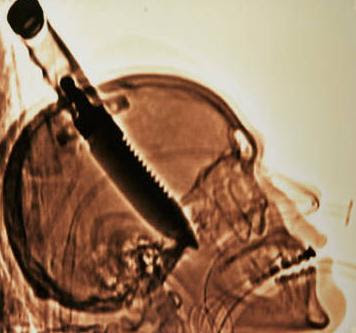

14. Pisau itu haram?

Seorang anak laki-laki berusia 16 tahun ditikam di kepala dengan pisau pada tahun 2007. Insiden supermarket yang tidak biasa.